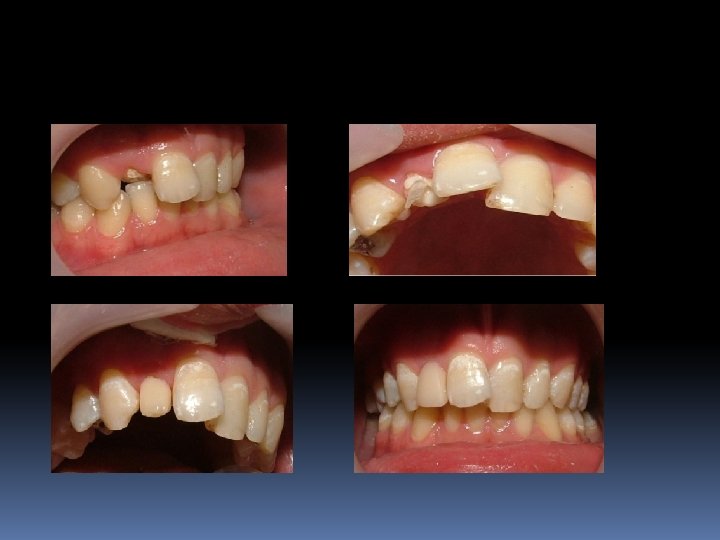

“Post-Kor” restorasyonlarının endikasyonları 1. Aşırı derecedeki madde kayıplarında, 2. Travma sonucu oluşan kron kırıklarında 3. Erozyon gibi aşınmalar sonucu derin madde kayıplarında 4. Diş akslarının düzeltilmesinde, 5. Teleskop kronların kullanımında, dişlerin “post-kor” yada yalnız “kor” alt yapısı ile restore edilmesi gerektiğinde.